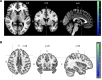

BackgroundAlcohol use disorder (AUD) is a chronic, relapsing brain disorder that accounts for 5% of deaths annually, and there is an urgent need to develop new targets for therapeutic intervention. The glucagon-like peptide-1 (GLP-1) receptor agonist exenatide reduces alcohol consumption in rodents and nonhuman primates, but its efficacy in patients with AUD is unknown.MethodsIn a randomized, double-blinded, placebo-controlled clinical trial, treatment-seeking AUD patients were assigned to receive exenatide (2 mg subcutaneously) or placebo once weekly for 26 weeks, in addition to standard cognitive-behavioral therapy. The primary outcome was reduction in number of heavy drinking days. A subgroup also completed functional MRI (fMRI) and single-photon emission CT (SPECT) brain scans.ResultsA total of 127 patients were enrolled. Our data revealed that although exenatide did not significantly reduce the number of heavy drinking days compared with placebo, it significantly attenuated fMRI alcohol cue reactivity in the ventral striatum and septal area, which are crucial brain areas for drug reward and addiction. In addition, dopamine transporter availability was lower in the exenatide group compared with the placebo group. Exploratory analyses revealed that exenatide significantly reduced heavy drinking days and total alcohol intake in a subgroup of obese patients (BMI > 30 kg/m2). Adverse events were mainly gastrointestinal.ConclusionThis randomized controlled trial on the effects of a GLP-1 receptor agonist in AUD patients provides new important knowledge on the effects of GLP-1 receptor agonists as a novel treatment target in addiction.Trial registrationEudraCT: 2016-003343-11. ClinicalTrials.gov (NCT03232112).FundingNovavi Foundation; Research Foundation, Mental Health Services, Capital Region of Denmark; Research Foundation, Capital Region of Denmark; Ivan Nielsen Foundation; A.P. Moeller Foundation; Augustinus Foundation; Woerzner Foundation; Grosserer L.F. Foghts Foundation; Hartmann Foundation; Aase and Ejnar Danielsen Foundation; P.A. Messerschmidt and Wife Foundation; and Lundbeck Foundation.